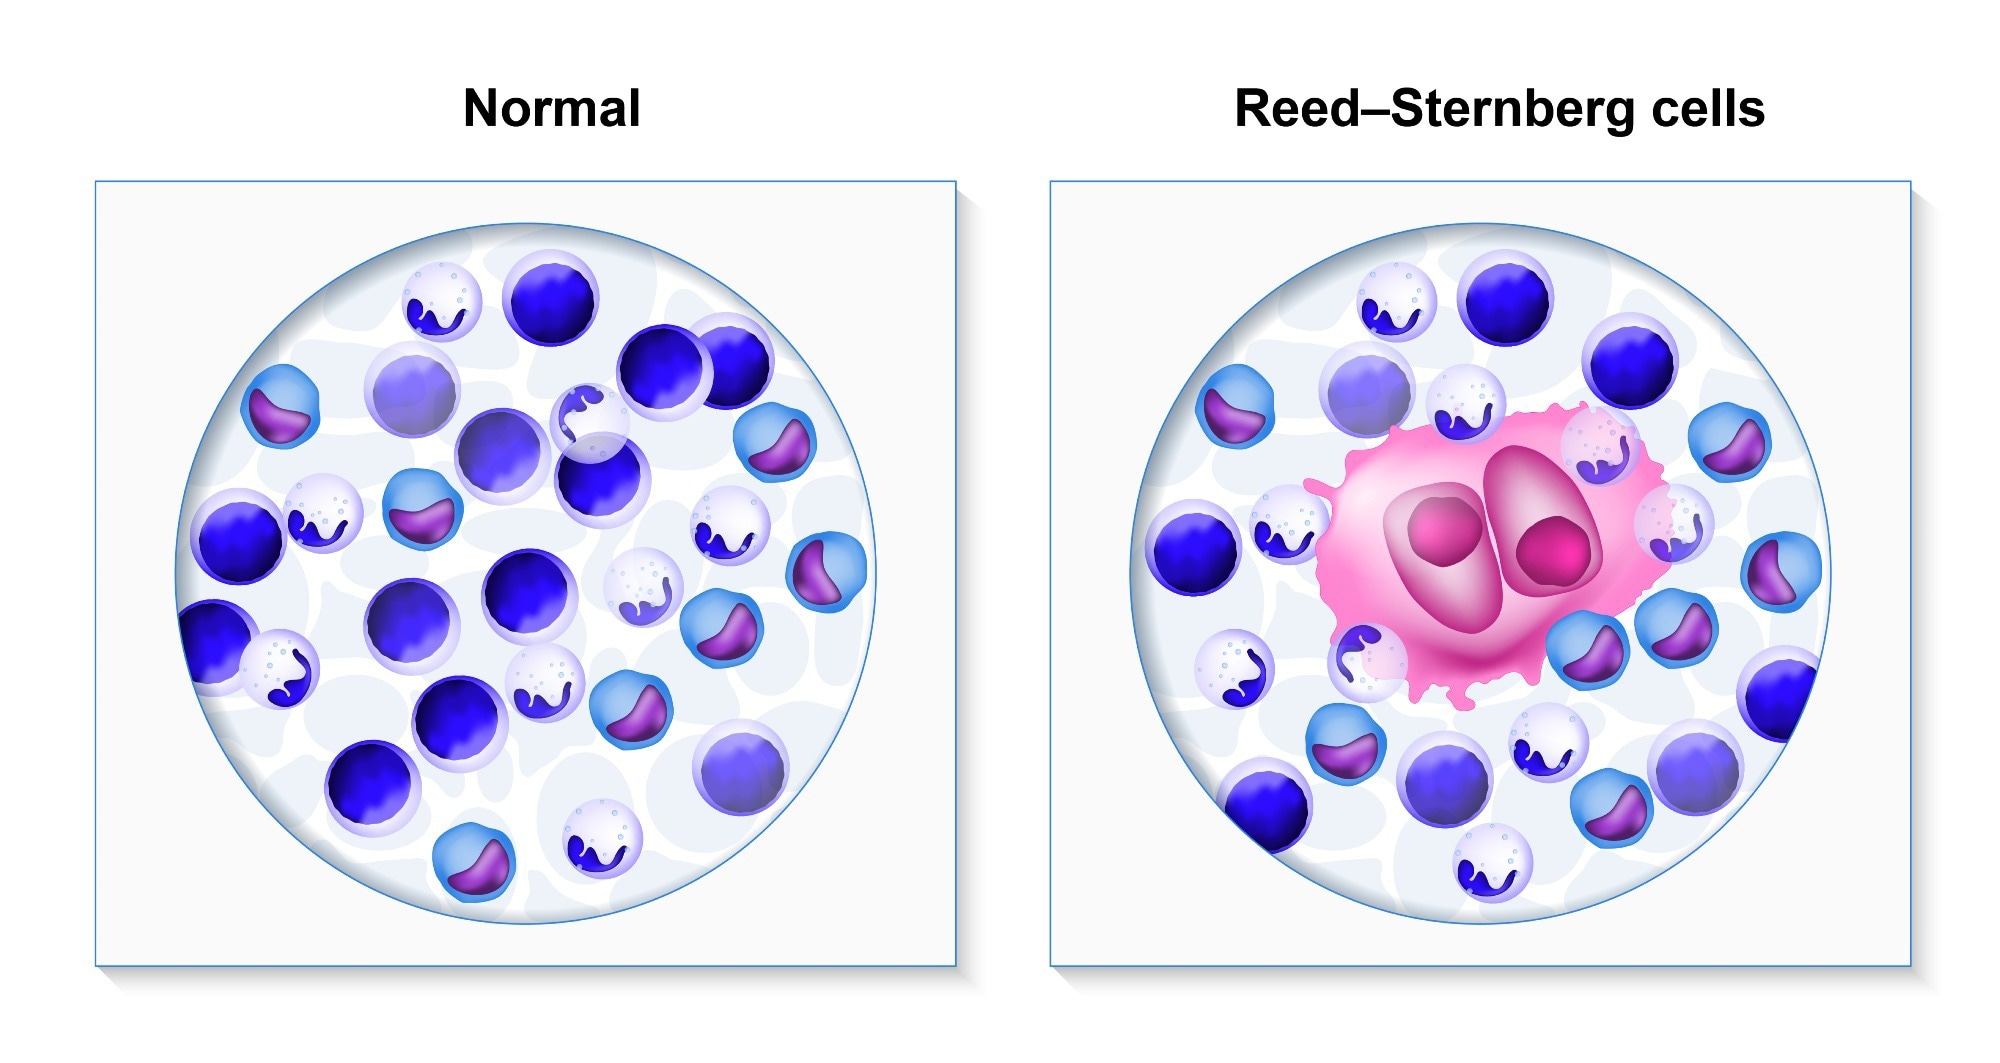

In cHL, tumor cells are primarily comprised of Reed-Sternberg (RS) cells that originate from mature B-cells. Despite this origin, RS cells typically appear much larger than B-cells due to the presence of multiple nuclei.

Hodgkin's lymphoma. biopsy healthy human cells and lymphoma patient. Reed-Sternberg and other white blood cells. Image Credit: Designua / Shutterstock

Hodgkin's lymphoma. biopsy healthy human cells and lymphoma patient. Reed-Sternberg and other white blood cells. Image Credit: Designua / Shutterstock